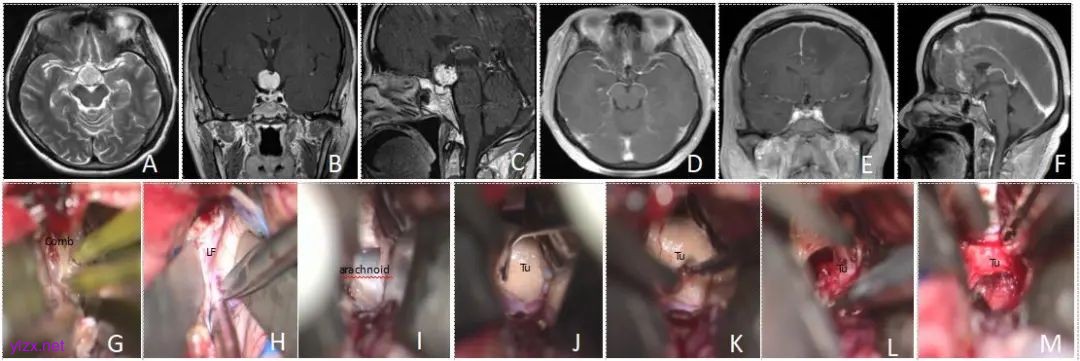

1.3 手术方法 TCA手术:依据肿瘤位置、大小及生长模式,选择翼点入路、额部纵裂入路、额下入路或胼胝体-透明隔-穹隆间入路进行手术。TCA适用于处理横向扩展至颈内动脉分叉、与下丘脑或视交叉密切相邻的深部肿瘤(图2)。

图2 经纵裂入路手术切除颅咽管瘤资料 Comb,鸡冠;LF,纵裂;arachnoid,蛛网膜;Tu,肿瘤。A~C,术前MRI影像提示鞍上-下丘脑实性占位性病变,明显增强,肿瘤起源于下丘脑垂体漏斗处,视交叉受压前移,考虑为颅咽管瘤;D~F,术后复查MRI影像提示肿瘤切除干净,垂体柄在位,未见残留;G~M:经纵裂入路手术切除肿瘤情况。G,切开硬膜后沿中线先找到鸡冠;H,分开纵裂;I,见到终板并切开见到蛛网膜,吸除脑脊液;J,切开蛛网膜并向四周分离后见到肿瘤,后方为大脑前动脉;K~L,分块切除肿瘤,瘤内减压;M,切除剩余肿瘤。Fig.2 Traditional craniotomy approach for treating craniopharyngioma